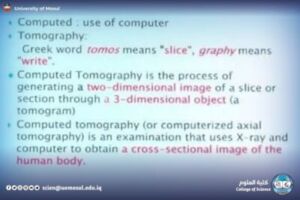

CT: an explanation of how to take multiple clips, the idea of the HU, and its role in imaging the brain, abdomen, and lung.